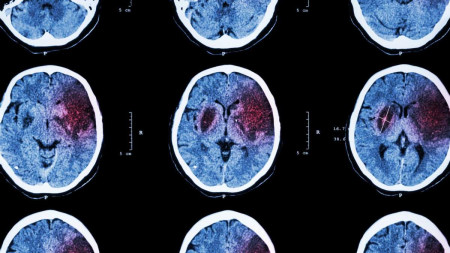

Учені зі США встановили, що у хворих на COVID-19 скорочується обсяг сірої речовини у фронтально-скроневій нейронній зоні мозку. Це і є причиною певної недієздатності пацієнтів навіть після одужання.

Вчені вважають, що, вимірюючи об'єм сірої речовини по знімках КТ, можна прогнозувати перебіг захворювання і призначати терапію.

Сіра речовина мозку відіграє важливу роль в обробці інформації, функції та комунікації нейронів. Основний удар по сірій речовині внаслідок коронавірусу припадає саме на фронтальну зону.

Нацковці проаналізували результати комп'ютерної томографії 120 пацієнтів з неврологічними проблемами, 58 з яких перехворіли на коронавірус у важкій формі. І застосували морфометричний аналіз, що дозволяє використовувати статистичні методи для вивчення вибірки помірних розмірів.

Аналіз показав, що у пацієнтів з високим рівнем недієздатності знижений об'єм сірої речовини в верхніх, медіальних і середніх лобових звивинах до моменту виписки і через 6 місяців. Також обсяг сірої речовини в цих ділянках виявився значно менше у хворих, які пройшли кисневу терапію.

Водночас зменшення обсягів сірої речовини виявили у верхніх, медіальних і середніх лобових звивинах у пацієнтів з підвищеною ажитацією (моторне занепокоєння, потреба в русі, - ред.). Ймовірно, ці зміни в мозку можуть лежати в основі афективних розладів, які часто виникають у пацієнтів з COVID-19.